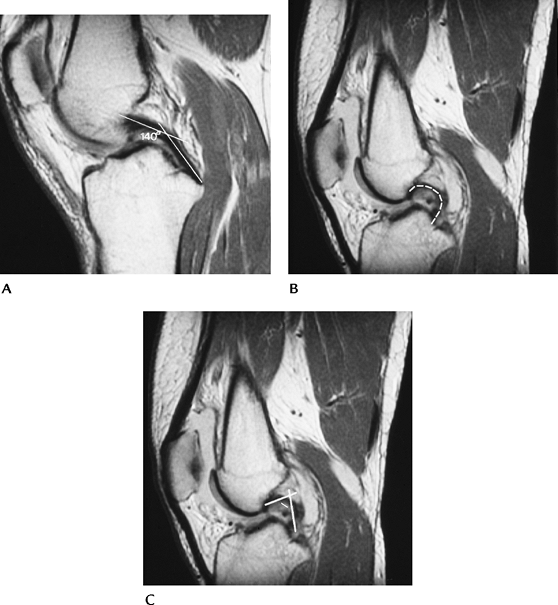

Ligament and Tendon Injuries: Anterior Cruciate Ligament—Acute (Secondary Features)

Numerous secondary signs have been described to improve accuracy and fully evaluate ACL injuries:

Joint effusion

Angulation of PCL—acute angle in upper PCL forming “?”

Abnormal PCL angle—normal 113 to 114 degrees; less than 105 degrees 86% specific for ACL tear

Anterior subluxation

Bone bruise—lateral compartment 97% specific

Second fractures (Fig. 5-13)

Deep femoral notch (>1.5 mm)

MCL tear

Meniscal tears

FIGURE 5-31 (A) Normal PCL with an angle (lines) of 140 degrees. Normal greater than 113 to 114 degrees. (B) ACL tear with hooked PCL (broken line). (C) ACL tear with hooked PCL and angle (lines) of less than 90 degrees.